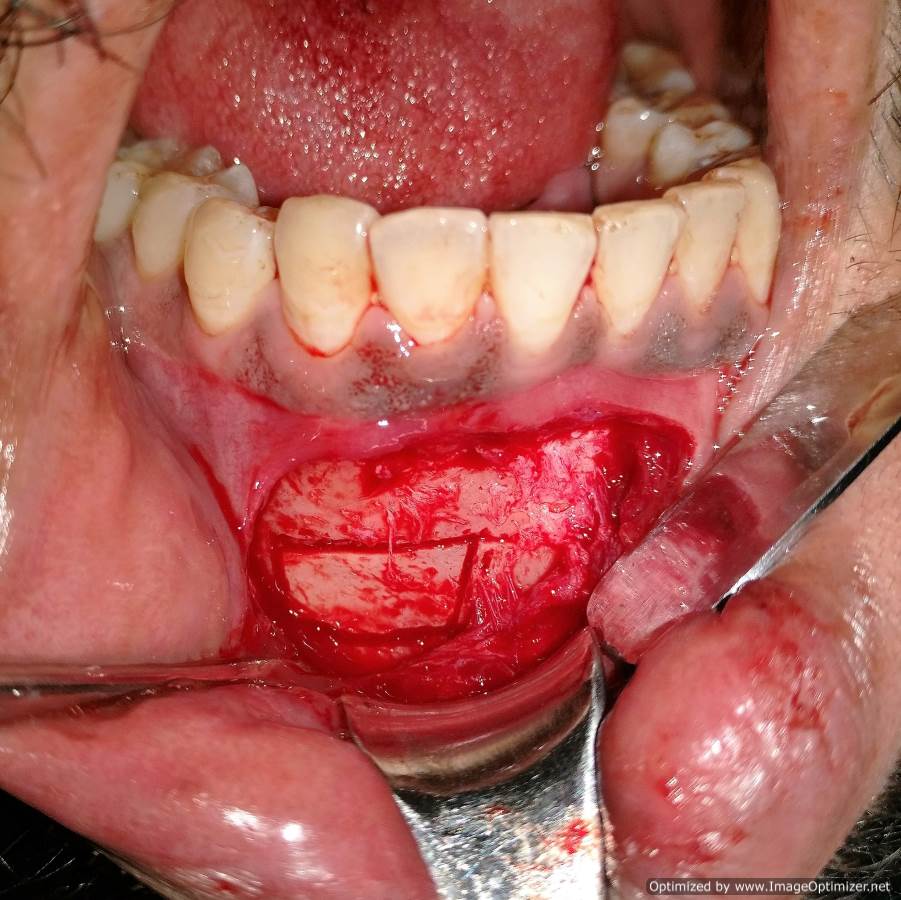

Dental Implant Case Report -03

Home / Case Report / Implant / Dental Implant Case Report -03